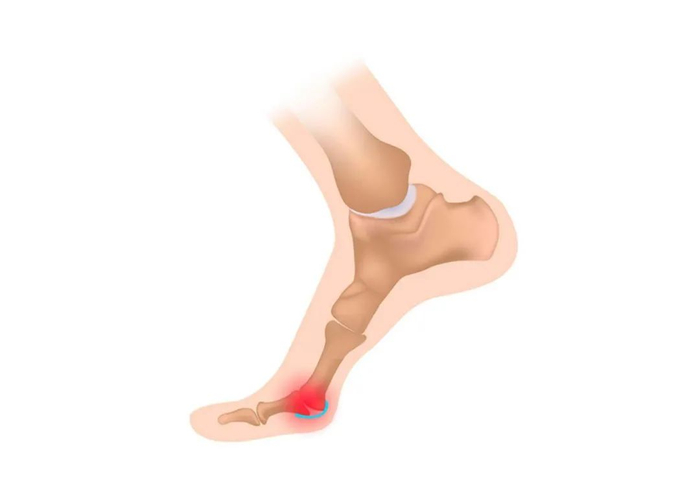

足底筋膜炎就是大众跑者最常见的足踝部位的伤痛,它主要表现为足底不适,在晨起时尤其明显,作为一种过度使用的劳损性问题,足底筋膜炎可以说困扰着很多跑者,并且一旦发生这个伤病,往往病程迁延,时好时坏。

足底筋膜就是位于足底的软组织,它起自脚跟处的跟骨,向前止于脚趾,由于脚趾头有五个,足底筋膜向前分叉为五束,足底筋膜的主要功能是缓冲,同时也协助维持足弓。

● 疼痛的具体位置实在在足跟靠内侧处,这里恰恰是足底筋膜从足跟发出的起点处,偶尔也有患者会反映疼痛在足底中部;